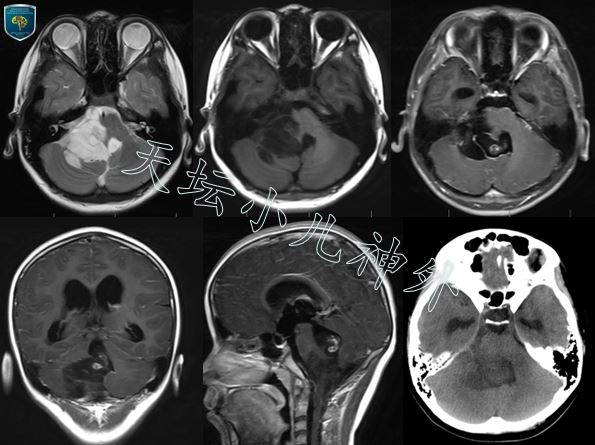

图1:头颅CT显示:第四脑室、右侧桥臂占位,稍低密度,室管膜瘤?星形细胞瘤?头颅MRI显示:C2水平椎管内,枕骨大孔,右侧小脑半球,脑干及四室内团块状影,边界清晰,增强扫描可见不规则强化,大小约46x40x70mm,室管膜瘤?胶质瘤?